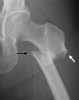

Bisphosphonate therapy

Bisphosphonates are a class of drugs that prevent the loss of bone density, used to treat osteoporosis and similar diseases. They are the most commonly prescribed drugs used to treat osteoporosis. [Source: Wikipedia ]